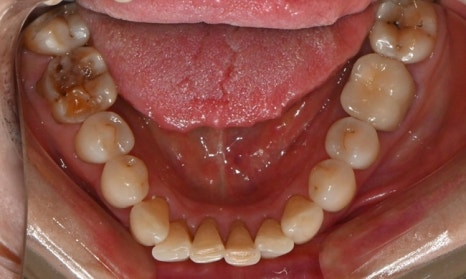

본 환자는 70세 여환으로 가만히 입을 다물고 있을 때 화난 것 처럼 보인다고 해서 튀어나온 앞니를 조금 넣고 싶다는 주소로 내원하셨습니다. 전체적인 치아 및 잇몸 상태를 검진해본 결과, 마모되어 깨진 치아도 있었고, 치경부(치아와 잇몸 사이 경계 부위)가 마모되어 파여 있는 부위도 많았습니다.

2025.2.3. 초진

교정 치료를 시작하기 전에 위아래 깨진 어금니는 보철 치료를 시행하였고, 치경부는 레진 치료를 시행하였습니다. 거의 뿌리의 신경관 근처까지 파여있던 치아가 치경부 레진 치료로 자연스럽게 수복이 되었습니다.

치경부 레진 치료 전후